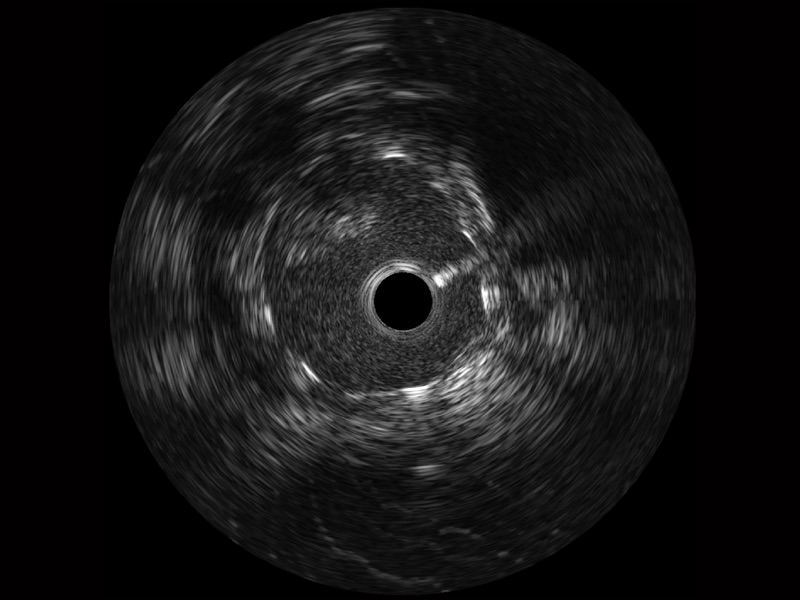

• 1xBET宽频IVUS图像

对比传统IVUS导管成像,1xBET宽频IVUS图像的近场支架梁显影更细腻,远场中膜外血管仍清晰可辨,兼顾远中近,兼顾分辨力与穿透深度